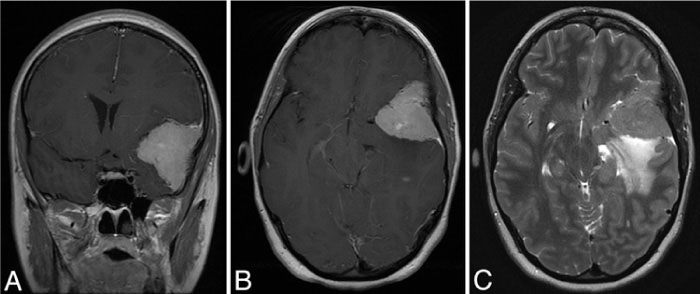

偶然发生的脑膜瘤,顾名思义,是在脑成像上诊断的,通常是脑部的磁共振图像,没有组织病理学证实。虽然影像学表现通常很有特点,但许多病变在影像学上可以模仿脑膜瘤的表现(图1和图2)。如果选择保守方法,这种可能性强调了初始密切随访评估的重要性。脑膜瘤的两个经典鉴别诊断是血管外皮细胞瘤和脑膜转移。血管外皮细胞瘤是一种少见的颅内恶性肿瘤,据信占全部原发性脑膜肿瘤的2%-3%。血管外皮细胞瘤较初被认为是脑膜瘤的一个亚组(血管母细胞变型),但自1993年以来,世卫组织将它们归类为一个独特的实体。血管外皮细胞瘤以其侵袭性、高复发率和潜在的转移而闻名。诊断时的中位生存期约为13年。

图2:轴位t1加权磁共振成像,增强显示轴外实性肿块,颞骨局灶性受累(箭头)。这个病变是一个成骨细胞瘤,在影像学上类似脑膜瘤。

硬脑膜转移也可以看起来像脑膜瘤,有相似的增强模式和硬脑膜尾。据估计,在尸检时发现8%-9%的晚期全身性癌症患者有硬脑膜转移临床发病率较低,因为许多这些病变是无症状的。脑膜转移较常见的原发性肿瘤是腺癌、肺癌和乳腺癌。许多其他疾病也可以模仿脑膜瘤,包括淋巴瘤、室管膜瘤、肉瘤、骨膜成骨细胞瘤、炎性假瘤、Rosai-Dorfman病定期的放射学和临床监测可以帮助确定病变的行为,并可能提高良性脑膜瘤的推定诊断的不确定性。此外,根据解剖位置,还应考虑其他诊断。例如,对于桥小脑角肿瘤,神经鞘瘤可以列入鉴别诊断;对于鞍区肿瘤,则应增加垂体腺瘤和颅咽管瘤。

该患者为27岁女性,长期非特异性头痛,神经系统检查正常。脑部磁共振成像显示有一个较大的蝶骨外侧翼脑膜瘤(图4)。肿块的较大直径为4.5厘米,并伴有明显的脑水肿和肿块效应。决定手术是因为肿瘤体积大,瘤周水肿,患者年龄小。